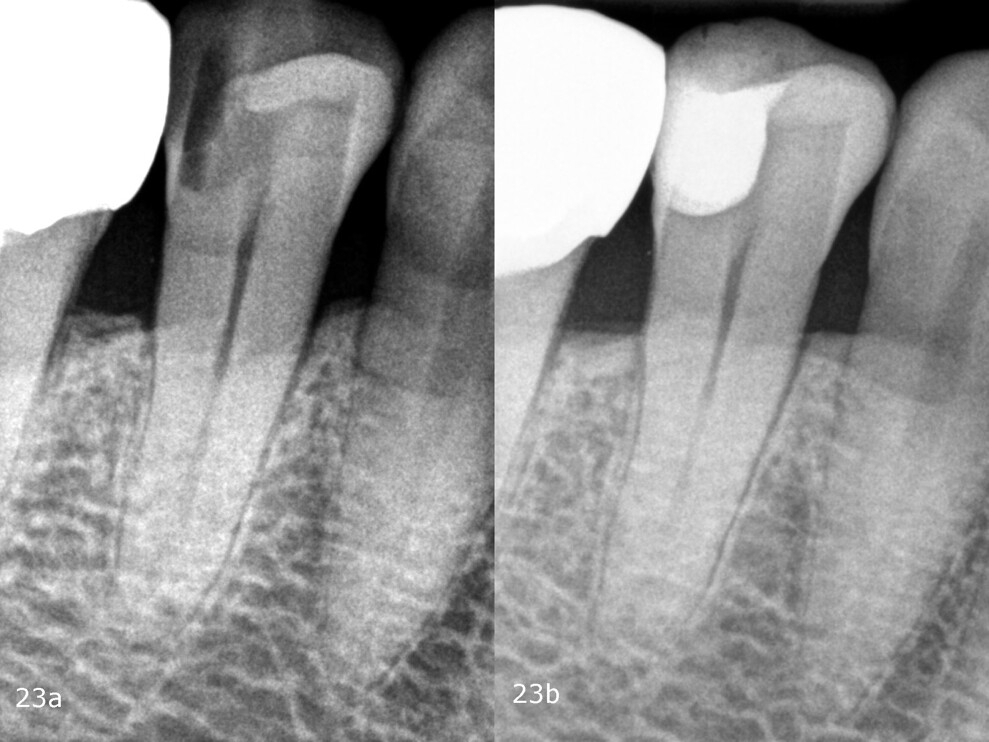

Comparison of the preoperative and postoperative radiographs demonstrates the quality of the treatment (Fig. 23). Owing to the excellent application properties of the thermo-viscous composite, the restoration does not contain any air bubbles. In addition, there is uniformity between the two composites used in terms of visibility on radiographs, and overall, the restoration appears homogeneous, there being no visible transitions between the base flowable composite and the bulk-fill composite. The preoperative radiograph did not show the full extent of the lesion. Only during the treatment did it become apparent that very thorough preparation had to be carried out in order to completely remove the affected tooth structure. In order to maintain the vitality of the pulp, desensitisation was carried out before the actual composite restoration.

Figs. 23a & b: Pre- and post-op radiograph.